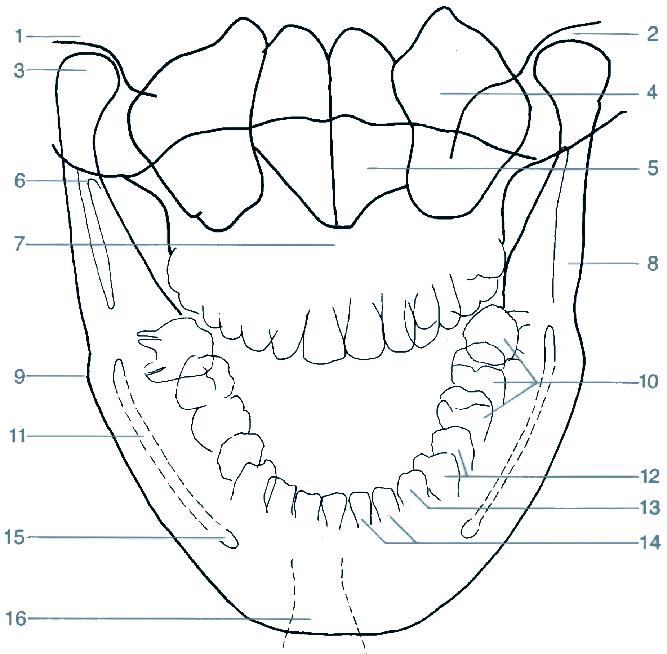

1 articulatio temporomandibularis (čelistní kloub)

2 caput mandibulae (hlavice dolní čelisti)

3 processus coronoideus (krkavčitý výběžek)

4 alveolární okraj

5 foramen mandibulae

6 protuberantia mentalis (bradový výběžek)

7 cavitas dentis (pulparis) (dřeňová dutina zubu)

8 canalis radicis dentis (zubní kanálek)

9 foramen apicis radicis dentalis

10 foramen mentale

11 canalis mandibulae (kanál v dolní čelisti)

12 angulus mandibulae (úhel dolní čelisti)

1 stříška kloubní jamky čelistního kloubu

2 articulatio temporomandibularis (čelistní kloub)

3 caput mandibulae (hlavice dolní čelisti)

4 sinus maxillaris (dutina horní čelisti)

5 cavitas nasi (nosní dutina)

6 processus coronoideus (krkavčitý výběžek)

7 maxilla (horní čelist)

8 ramus mandibulae (rameno dolní čelisti)

9 angulus mandibulae (úhel dolní čelisti)

10 dentes molares (stoličky)

12 dentes premolares (premoláry)

13 dens caninus (špičák)

14 dentes incisivi (řezáky)

15 foramen mentale

16 tuberculum mentale (sumace s projasněním trachey)

19 canalis radicis dentis (kořenový kanál)

20 cavitas dentis (pulparis) (dřeňová dutina zubu)

21 dentin korunky (zubovina)

22 sklovina 23 foramen mentale

24 radix dentis (zubní kořen)

25 dentes incisivi (řezáky)

26 dens caninus (špičák)

27 dentes premolares (premoláry)

28 dentes molares (stoličky)

10 recessus alveolaris (dno dutiny horní čelisti) 11 sinus maxillaris (dutina horní čelisti) 12 fossa pterygopalatina 13 processus pterygoideus (křídlový výběžek kosti klínové) 14 angulus mandibulae (úhel dolní čelisti) 15 stín jazyka 16 canalis mandibulae (kanál v dolní čelisti) 17 os hyoideum (jazylka) 18 foramen apicis radicis dentis